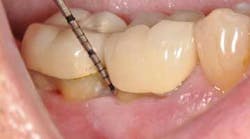

• The use of biologic modifier such as PDGF-BB as an adjunct to bone particulate and collagen membranes

In the present case, a 61-year-old male was referred to my periodontal office by his general dentist for an evaluation of pain and bleeding to the lower right mandible. The patient’s medical history consisted of controlled type 2 (noninsulin dependent) diabetes and hypertension. Upon review of the panoramic radiograph (figure 1), the periodontal defects are not clearly evident, thus showing the importance of proper radiographs to detect periodontal defects. The periapical radiographs (figure 2) clearly show subgingival calculus, grade 1 furcation on No. 30, grade 3 furcation on No. 31, and an advanced intrabony defect on the distal of No. 30. Clinically, there was no mobility to either No. 30 or 31 and both teeth were vital. Tooth vitality is an extremely important diagnostic factor in treatment panning. Periodontal charting of the lower right was also performed, and the lower right exhibited bleeding and inflammation (figure 3).